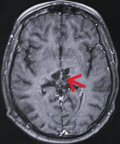

Diagnostic assessment: magnetic resonance imaging of the brain demonstrated an infiltrative thalamo-peduncular lesion with hyperintensity on T2/FLAIR sequences and faint enhancement on post-contrast T1, raising concern for an infiltrative high-grade glioma and creating diagnostic uncertainty (Figure 1, Figure 2). A stereotactic biopsy was subsequently performed. Initial histological evaluation suggested a high-grade glioma; however, immunohistochemical staining revealed strong positivity for CD117, PLAP, and OCT4, findings consistent with a pure germinoma (Figure 3, Figure 4). Staging with thoraco-abdominopelvic CT identified nonspecific pulmonary micronodules (Figure 5), while serum tumor markers remained within normal limits (Table 1). As shown above, the patient's LDH level is elevated compared to the reference range, while both β-HCG and α-FP are within normal limits. These values are important for the diagnostic evaluation and ongoing management of intracranial germ cell tumors.

Figure 1: contrast-enhanced brain magnetic resonance image showing a thalamo-peduncular lesion: axial T1-weighted post-contrast magnetic resonance image demonstrating a thalamo-peduncular mass with heterogeneous patchy enhancement and multiple small cystic components (red arrow)